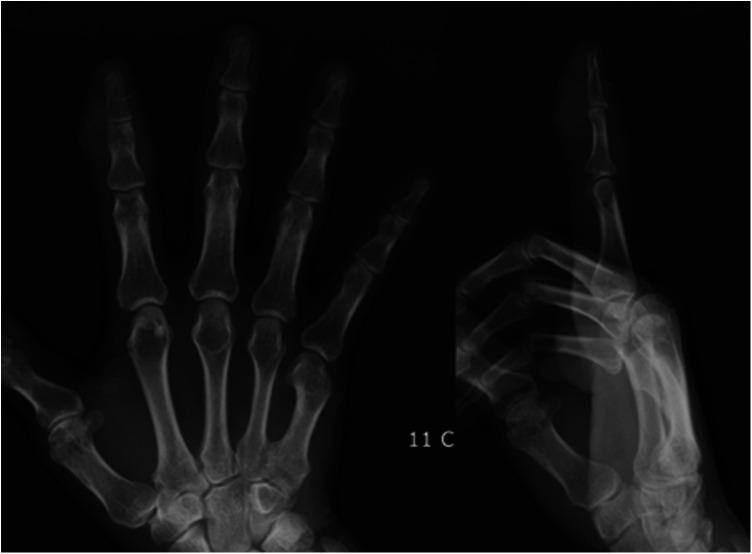

Calcific tendonitis rarely occurs in the fingers, and it is easily misdiagnosed. Herein we describe the case of a patient with multiple calcific lesions within the flexor digitorum superficialis and the extensor digitorum tendons of the distal interphalangeal joints of the right index finger, and the surgical treatment of those lesions.

The patient was a 66-year-old man who reported pain and swelling in his right index finger for one year. He was diagnosed with chronic calcific tendonitis based on his symptoms and radiology images. He was successfully treated surgically, and histopathological examination confirmed the diagnosis. After one month, the patient had healed well, and there was no recurrence.

钙化性肌腱炎很少发生于手指,且容易误诊。在此我们描述一例患者,其右示指远节指间关节的指浅屈肌腱和指伸肌腱内有多处钙化性病变,以及对这些病变的手术治疗。

患者为一名66岁男性,自述右示指疼痛、肿胀1年。根据其症状和影像学图像,诊断为慢性钙化性肌腱炎。他接受手术治疗后成功康复,组织病理学检查确诊。1个月后,患者愈合良好,无复发。